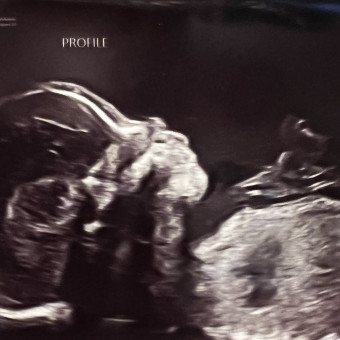

Haley & Thomas LaJoie

January 28, 2026